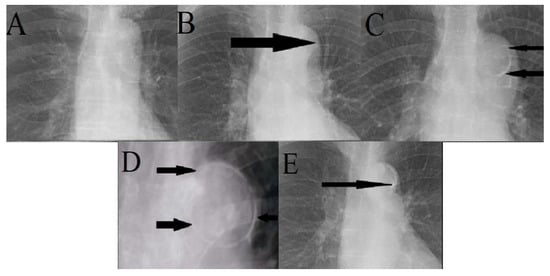

2.2. Measurement

- Ogawa, T.; Ishida, H.; Matsuda, N.; Fujiu, A.; Matsuda, A.; Ito, K.; Ando, Y.; Nitta, K. Simple evaluation of aortic arch calcification by chest radiography in hemodialysis patients. Hemodial. Int. 2009, 13, 301–306. [Google Scholar] [CrossRef] [PubMed]

- Hashimoto, H.; Iijima, K.; Hashimoto, M.; Son, B.K.; Ota, H.; Ogawa, S.; Eto, M.; Akishita, M.; Ouchi, Y. Validity and usefulness of aortic arch calcification in chest X-ray. J. Atheroscler. Thromb. 2009, 16, 256–264. [Google Scholar] [CrossRef] [PubMed]

- Inoue, T.; Ogawa, T.; Ishida, H.; Ando, Y.; Nitta, K. Aortic arch calcification evaluated on chest X-ray is a strong independent predictor of cardiovascular events in chronic hemodialysis patients. Heart Vessels 2012, 27, 135–142. [Google Scholar] [CrossRef]